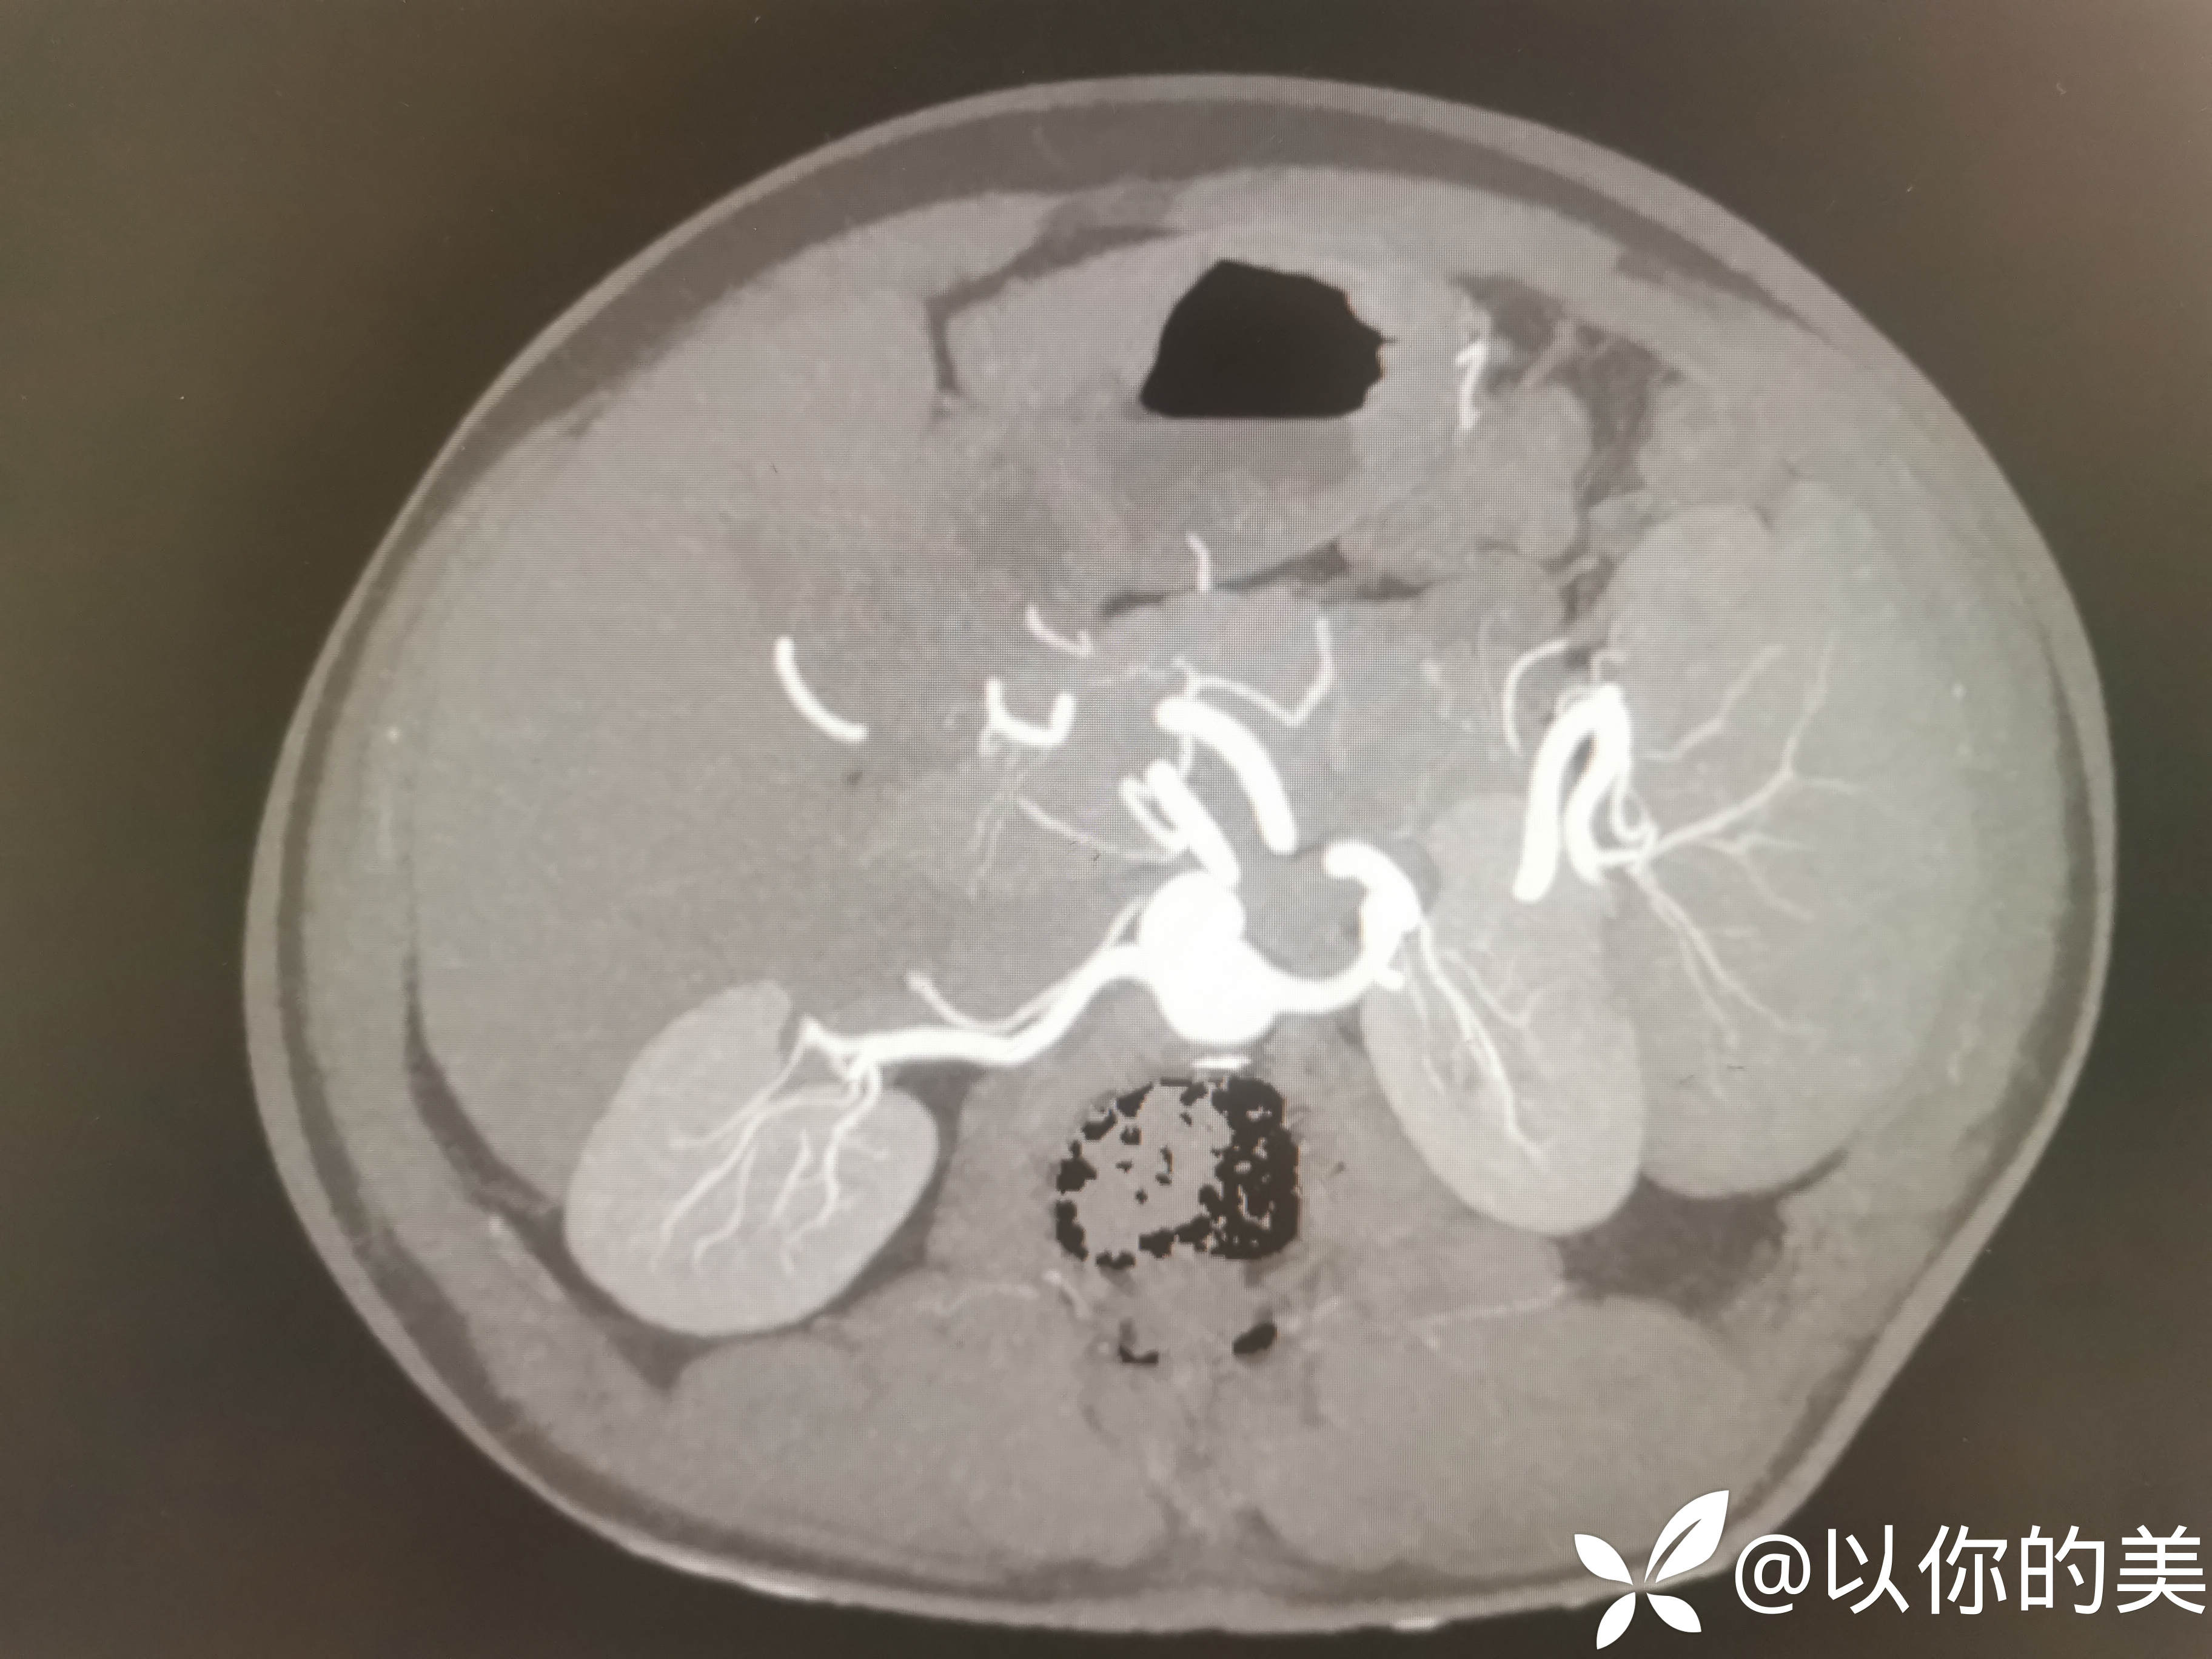

肾血管CTA:

肾血管CTA有无异常,行肾血管CTA意义何在?